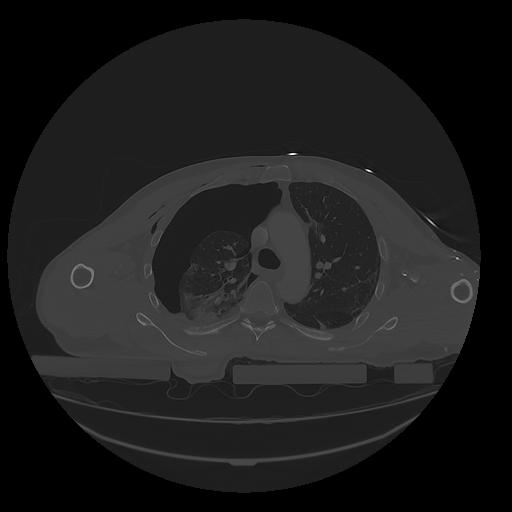

31 PULMON,CE,Vol,1.0,PULMON,,